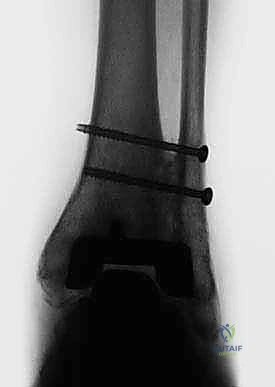

يتم هذا الدمج باستخدام مسمار نخاعي (Intramedullary Nail) طويل وقوي يُدخل من أسفل الكعب ليخترق العظام الثلاثة، ويتم تثبيته ببراغي قفلية لضمان أقصى درجات الثبات. الهدف من إلغاء الحركة في هذه المفاصل التالفة هو القضاء التام على الاحتكاك العظمي الذي يسبب الألم المبرح، مما يوفر للمريض قاعدة ثابتة وقوية للمشي.

5. التثبيت بالبراغي القفلية (Locking Screws)

لضمان عدم تحرك المسمار أو دوران العظام حوله، يتم تثبيت المسمار ببراغي عرضية تخترق العظام والمسمار معاً من الأعلى (في الساق) ومن الأسفل (في الكعب والكاحل). يتم استخدام جهاز التصوير الإشعاعي (C-arm) داخل غرفة العمليات للتأكد من الموضع المثالي لكل مسمار.